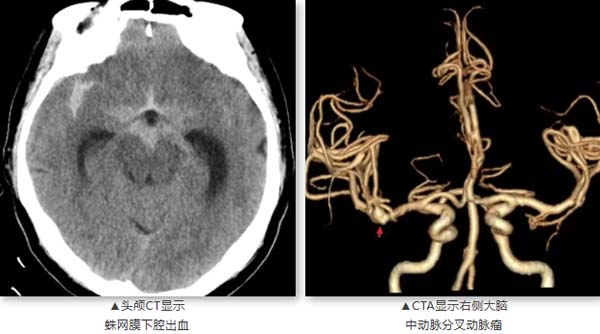

病例一为77岁女性患者,既往高血压病史。因“突发剧烈头痛伴恶心2天”前来清华大学附属垂杨柳医院急诊科就诊。头颅CT检查提示蛛网膜下腔出血,头颈动脉CTA提示右侧大脑中动脉M1段分叉处宽颈动脉瘤。神经外科脑血管病介入团队急诊为患者实施了全脑血管造影术(DSA),造影显示动脉瘤不规则,可见子囊,宽颈,主要累及下干。团队采取了支架辅助弹簧圈栓塞术,患者颅内“不定时炸弹”被成功拆除。动脉瘤达到致密栓塞,载瘤动脉通畅。住院半个月后顺利出院,无神经功能障碍。

▲术前DSA显示宽颈动脉瘤,有子囊,主要累及下干

▲术后DSA显示动脉瘤致密栓塞,载瘤动脉通畅